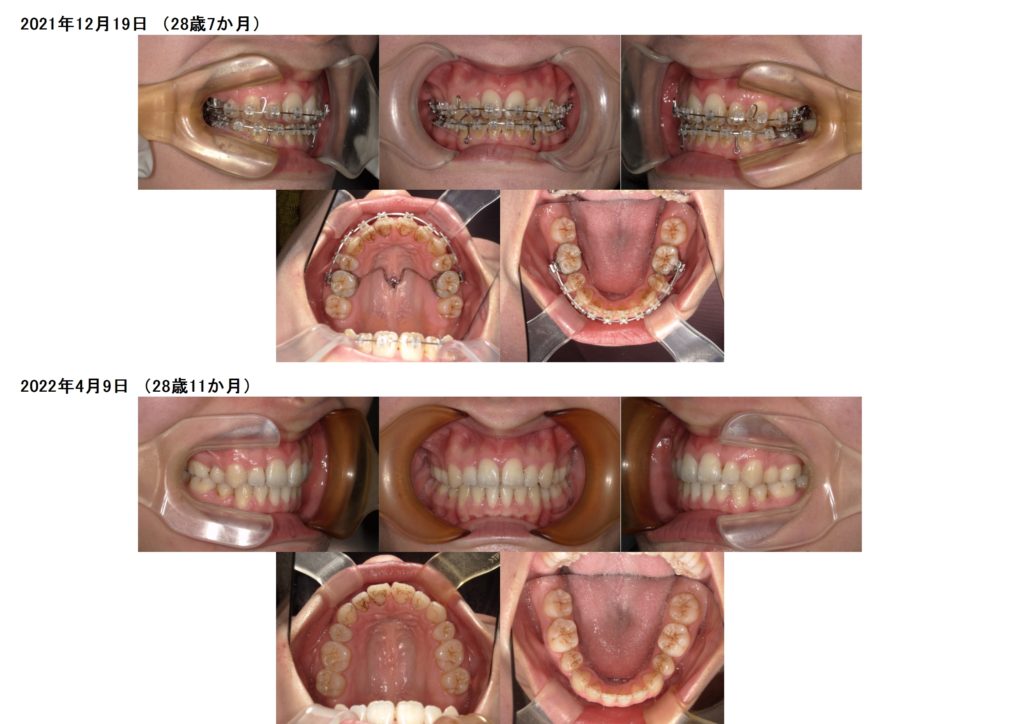

これからは噛み合わせの微調整に入ります。

ガッツリ動いた感じはないんですが、ジワジワと調整しまいます。